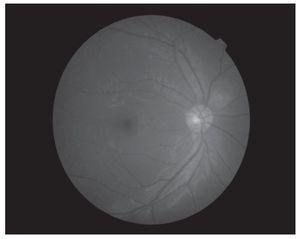

Hombre de 13 años de edad, sin antecedentes heredofamiliares ni personales patológicos de importancia. El motivo de consulta fue la disminución progresiva de la agudeza visual de meses de evolución, acompañado en ocasiones de dolor periocular intermitente. A la exploración física se encontró una talla de 1.52 m, la cual se encuentra dentro de la percentila 50 para la edad, así como una discreta braquidactilia en ambas manos. La exploración oftalmológica reveló: agudeza visual de 20/400 en ambos ojos y una agudeza visual mejor corregida de 20/30 y 20/40 respectivamente, con una refracción de -11.00 = -0.75X145° en OD y -11.00 = -2.50X5° en OI. La posición primaria de la mirada en ortoposición y los movimientos oculares fueron normales. La presión intraocular fue de 26 mmHg en OD y 21 mmHg en OI. El segmento anterior de ambos ojos bajo lámpara de hendidura, mostró una cámara anterior estrecha, tanto en la periferia como en el centro (Figuras 1a y 1b) con un ángulo iridocorneal en ambos ojos de 0 en los 360° (Figuras 2a y 2b). En segmento posterior de ambos ojos encontramos una excavación papilar de aproximadamente 6/10, con un defecto en la capa de fibras nerviosas evidenciada por las fotografías libres de rojo (Figuras 3a y 3b). El paciente fue tratado inicialmente mediante la realización de iridotomías con láser de YAG en ambos ojos y tratamiento tópico con una combinación brimonidina-timolol-dorzolamida, acudiendo nuevamente a consulta dos días posteriores al tratamiento encontrando una presión de 13 mmHg en ambos ojos con las iridotomías permeables (Figura 4).

¿ Figura 3b. OI. Polo posterior. Defecto en capa de fibras nerviosas.